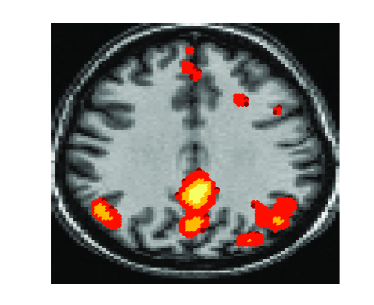

In this section we evaluate the performance of the proposed joint

matrices diagonalization algorithm on a resting state fMRI experiment

data set [20]. Data-driven methods were successfully

suggested and applied to fMRI data analysis. These methods consider

the fMRI time series measured at each voxel as a mixture of signals

localized in a small set of regions and other simultaneous

time-varying effects. They isolate the spatial brain activity by

estimating a mixing matrix and the sources that define the spatially

localized neural dynamics. Most data driven fMRI analysis methods

use a data matrix Y formed by vectorizing each time

series observed in every voxel creating a matrix Y of

dimension where is the number of time points and

the number of voxels, .

These methods consider Y as

the mixture and factorize it into latent sources through the

decomposition into matrices , a

mixing matrix A and a source matrix

X. Data-driven methods are suitable for the analysis of

fMRI data as they minimize the assumptions on the underlying structure

of the problem by decomposing the observed data based on a factor

model and a specific constraint. Different constraints have led to

different data-driven methods. For example, the maximum variance

constraint has led to principal component analysis (PCA)

[11], the independence constraint has led to independent

component analysis (ICA) [14] and sparsity constraint has

led to dictionary learning [13].

Recently, ICA has become a widespread data-driven method for fMRI analysis. It has led to temporal ICA (tICA, for the format of the data described above) and spatial ICA (sICA) [14]. In this experiment we applied the proposed joint diagonalization approach on twenty correlation matrices of size obtained from a data set of size . This data set was constructed from the slice 41, which we know contains the activated regions of the default mode network (DMN) [20]. For comparison we used the tICA approach. We can observe from figure 4 that both the proposed approach and tICA recovered the connected regions of the DMN; the posterior cingulate cortex (PCC), medial pre-frontal cortex (MFC), and right inferior parietal lobe (IPL). Since there is no gold standard reference for DMN connectivity available, we relied on the similarity of temporal dynamics of DMN based modulation profile with PCC representative time-series. The similarity measure used was correlation and it was estimated as for all the algorithms.